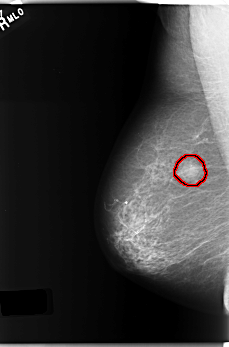

C_0231_1.RIGHT_MLO

FILE: C_0231_1.RIGHT_MLO.OVERLAY

TOTAL_ABNORMALITIES 1

ABNORMALITY 1

LESION_TYPE MASS SHAPE ROUND MARGINS ILL_DEFINED

ASSESSMENT 5

SUBTLETY 5

PATHOLOGY MALIGNANT

TOTAL_OUTLINES 1

BOUNDARY